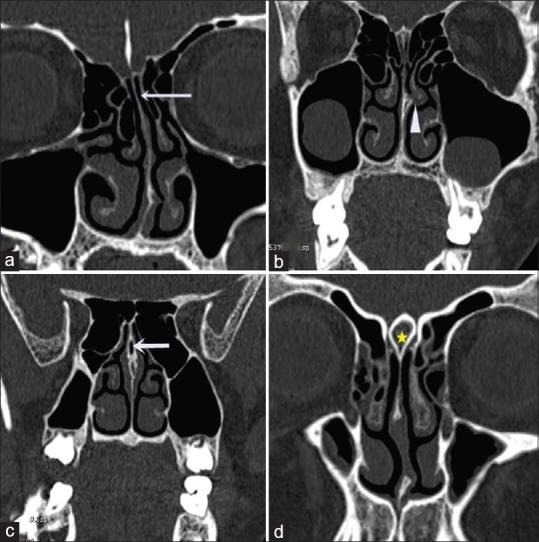

With the advent of functional endoscopic sinus surgery and coronal computed tomography (CT) imaging, more attention has been paid toward paranasal region anatomy. Detailed knowledge of anatomic variations in paranasal sinus region is critical for surgeons performing endoscopic sinus surgery as well as for the radiologist involved in the pre- and post-operative assessment. The anatomical variants with some accompanying pathologies would directly influence the success of diagnostic and therapeutic management of paranasal sinus diseases. Our study intends to explore the anatomy of paranasal air sinus through CT and to describe its variants, which may predispose to chronic sinusitis and complications in endoscopic sinonasal surgery.

Among 250 study population, 100 were females and 150 males. Among these 423 cases of anatomical variants were observed. The most common anatomical variants were pneumatization of the middle nasal turbinates 30.73%. This is followed by agger nasi cells 21.64%, Haller's cells 22.91%, septal deviation 21.91%, and sphenoid sinus septation (20.18%).

CT is the gold standard in the radiologic investigation of the paranasal sinuses, sinonasal lesions, and inflammatory disease or pre- and post-surgical assessment. It has the capability of disclosing in greatest detail any anatomical variations, which could be causing or precipitating the sinusitis.